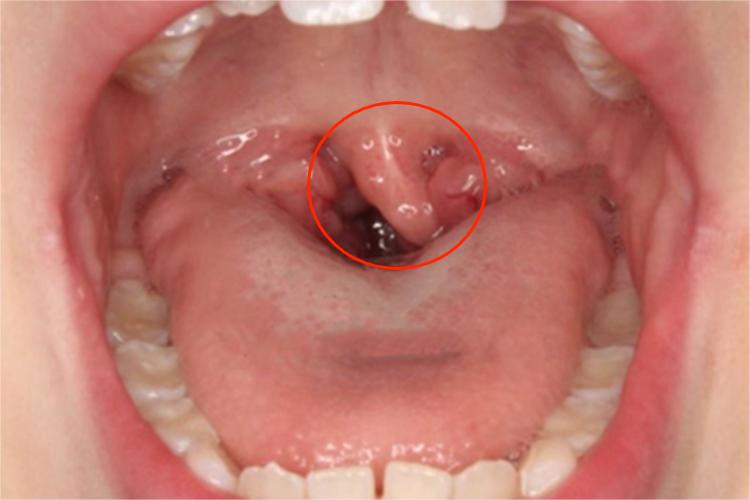

悬雍垂过长症局部检查见悬雍垂细长,且较松弛,常伴有咽部不适感或异物感,多因口咽部及扁桃体的慢性炎症长期刺激所致。

检查咽部时可见悬雍垂部较松弛、细长,有时也可出现较粗的形态,其末端可与舌根部接触,较长时,软腭上举时也无法离开舌根。